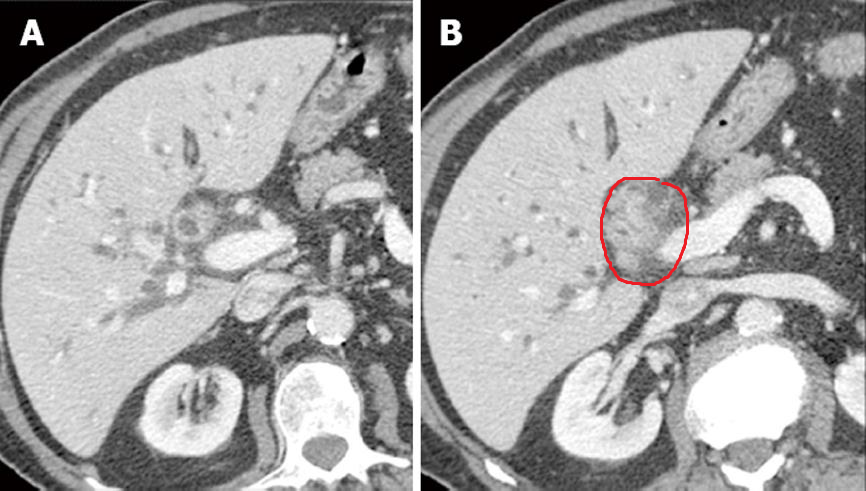

Min erfaring er at flesteparten har et avrundet utseende, mens færre har en infiltrativ vekst langs gangsystemet. Her er noen bilder for å eksemplifisere typiske utseender:

På CT-skanningene ser man tversnitt gjennom buken (kalles transversalplan eller axialplan). Jeg har markert med rødt omkring cholangiocarcinomene.

Noen av de over er ikke så enkle å avgrense, på nederste bilder er det med to snitt. I snittet til venstre er det tegn til infiltrativ vekst langs med gallegangsystemet i høyre leverlob. I tillegg har man den mer runde forandringen noen snitt nedenfor, så da blir det vanskelig med eksakte utmålinger.

Galleganger som er obstruerte blir fyllt med gallesludge, som er geleaktig galle. Dette kan likne på tumorvekst.

MR-skanning er noe bedre til avgrensning fordi man har bedre kontrast samt får hjelp av noe som heter diffusjonvektede sekvenser.

Så det er ikke alltid så lett med klatskintumorer, og det er sikkert derfor også at flere av PCIB sine pasienter ikke har vært målbare i henhold til recist.